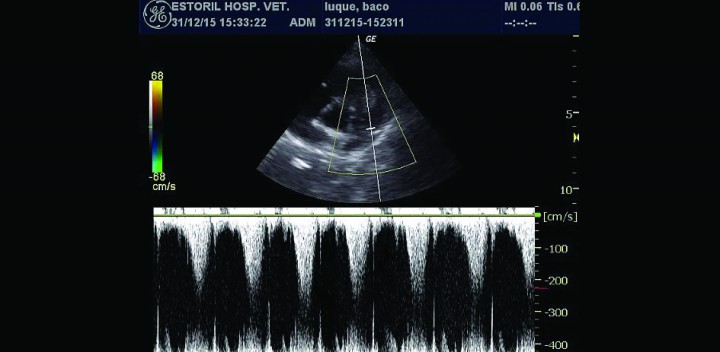

Figura 5

Doppler pulsado arteria pulmonar, flujo acelerado postobstrucción.

- Presencia de una masa intraluminal de dos por tres centímetros en tracto de salida derecho (Figs. 3B y 3C), que produce una obstrucción al flujo de salida y, por tanto, una reducción del caudal a través de la arteria pulmonar. El flujo laminar de salida a 1,4 m/s se vuelve turbulento a su paso por la masa, a la que rodea claramente (Fig. 4), provocando una aceleración del flujo hasta los 2,9 m/s (Fig. 5).